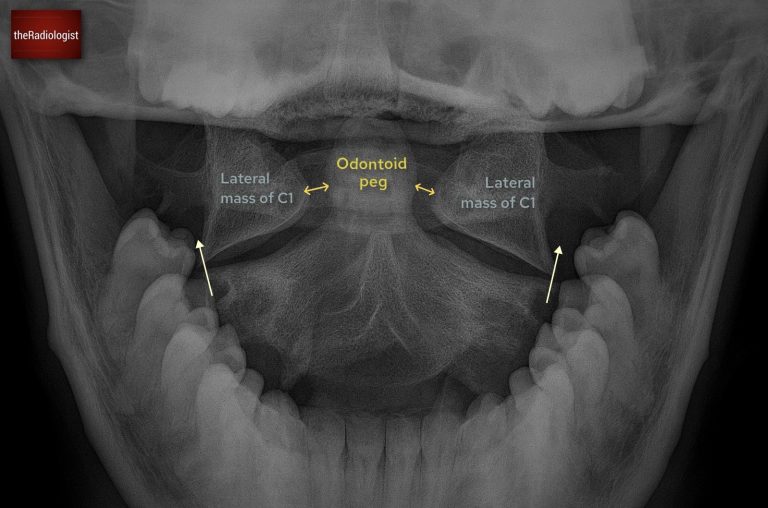

Open mouth peg view review

The open mouth odontoid, or ‘peg’ view, is performed to assess the dens of C2 and the articulation between C1 and C2. It is a critical projection, as fractures and subluxations at this level can be unstable and easily missed.

Annotated image of an open mouth peg view

1. Film adequacy

Confirm that the film is technically adequate. The teeth and occiput should not obscure the dens, and the lateral margins of C1 and C2 should be clearly visible. If the odontoid peg is not well seen, the view is non-diagnostic and should be repeated or further imaging obtained.

2. Alignment of lateral masses

This is a really important step: check that the lateral margins of C1 line up with those of C2. They should form a continuous vertical border on each side. Any offset suggests subluxation or fracture.

3. Symmetry around the dens

The odontoid peg should be equidistant from the lateral masses of C1. Asymmetry may reflect patient rotation, but can also represent true injury. If the lateral masses of C1 and C2 remain aligned and the only abnormality is unequal spacing between the dens and lateral masses, then the caue could be rotation rather than a true injury.

4. Integrity of the dens

Carefully inspect the cortex of the odontoid peg. It should appear smooth and continuous. Fractures may occur at the tip, through the body, or at the base of the dens. Subtle lucencies should not be dismissed, particularly in the trauma setting.

Be aware of artefacts that may mimic fracture. The ‘Mach effect’ produces false lines across the dens due to overlapping shadows. Superimposed teeth, tongue, or occipital bone can obscure detail or create apparent cortical breaks. Always interpret suspicious lines with caution and correlate with other views or cross-sectional imaging.